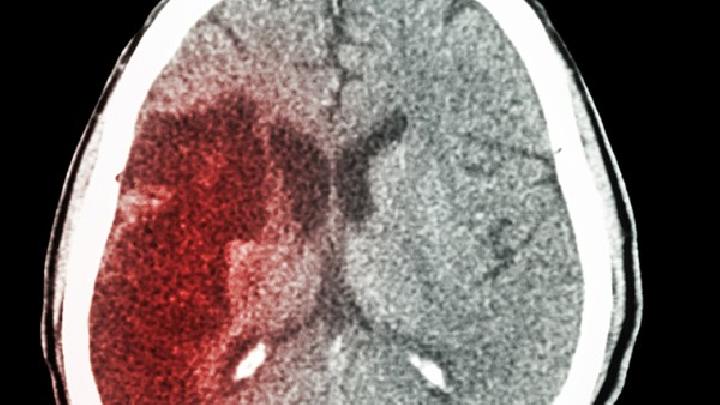

头部创伤是慢性硬膜血肿的主要原因,慢性硬膜血肿引起颅内高压、局部脑压力、脑循环阻塞、长期血肿、血管栓塞、坏死、结缔组织变性钙化,长期压迫脑组织,促进癫痫,导致脑萎缩和变性。

轻度脑挫伤可见额颞叶脑表面瘀血、水肿,软膜下有一点片状出血灶,蛛网膜或软膜常有裂纹,脑脊液呈血性。严重时脑皮质会形成血肿,损伤皮质血管栓塞,脑组织糜烂坏死,影响脑组织。从长远来看,它会导致脑萎缩。